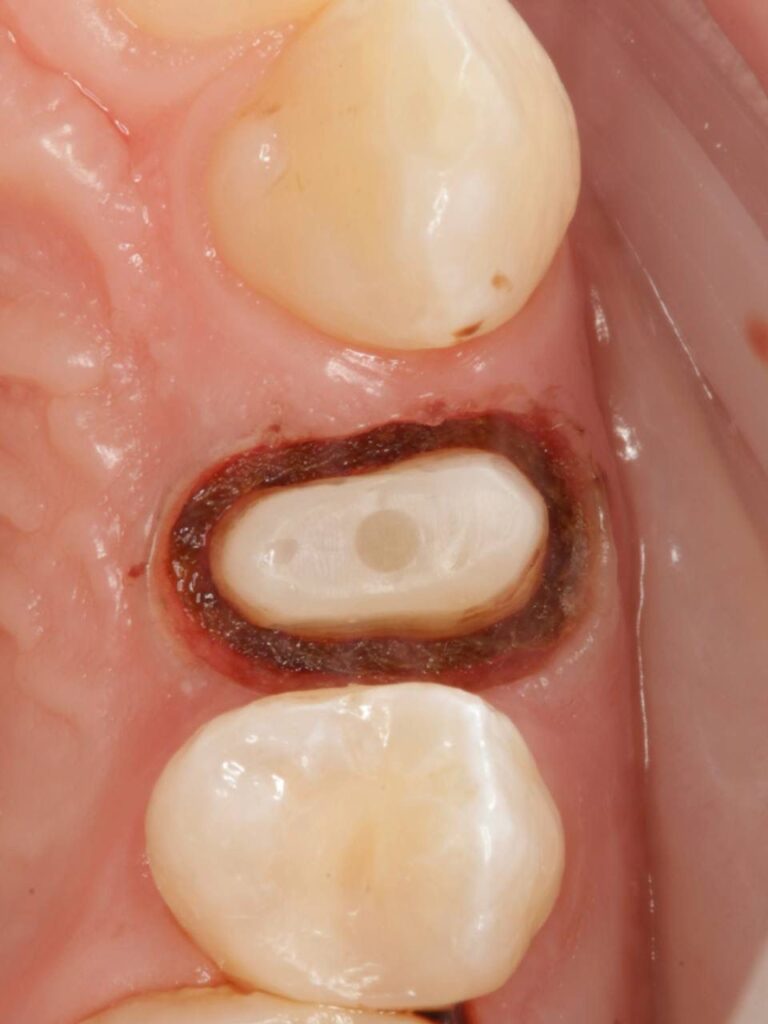

Специализация: терапия(эндодонтия), ортопедия, имплантология.